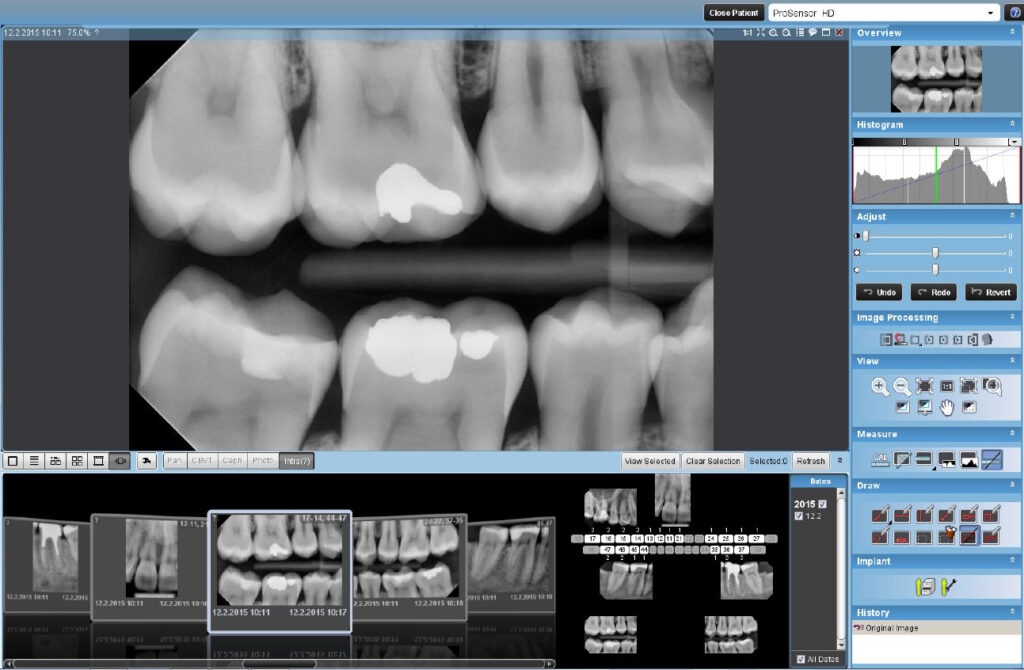

Pored standardnog panoramskog programa, mogući su i poboljšani: interproksimalni program – prošireni kontakti između zuba za lakšu detekciju karijesa, poboljšani ortognalni program – sa jasno vidljivim alveolarnim grebenom za poboljšanu dijagnostiku parodontalnih oboljenja SmartPan – OPT snimak registrovan 3D senzorom. Sa istom efektivnom dozom dobija se 10 OPT snimaka pa se bira najpogodniji za dijagnostiku.

2D - SNIMCI